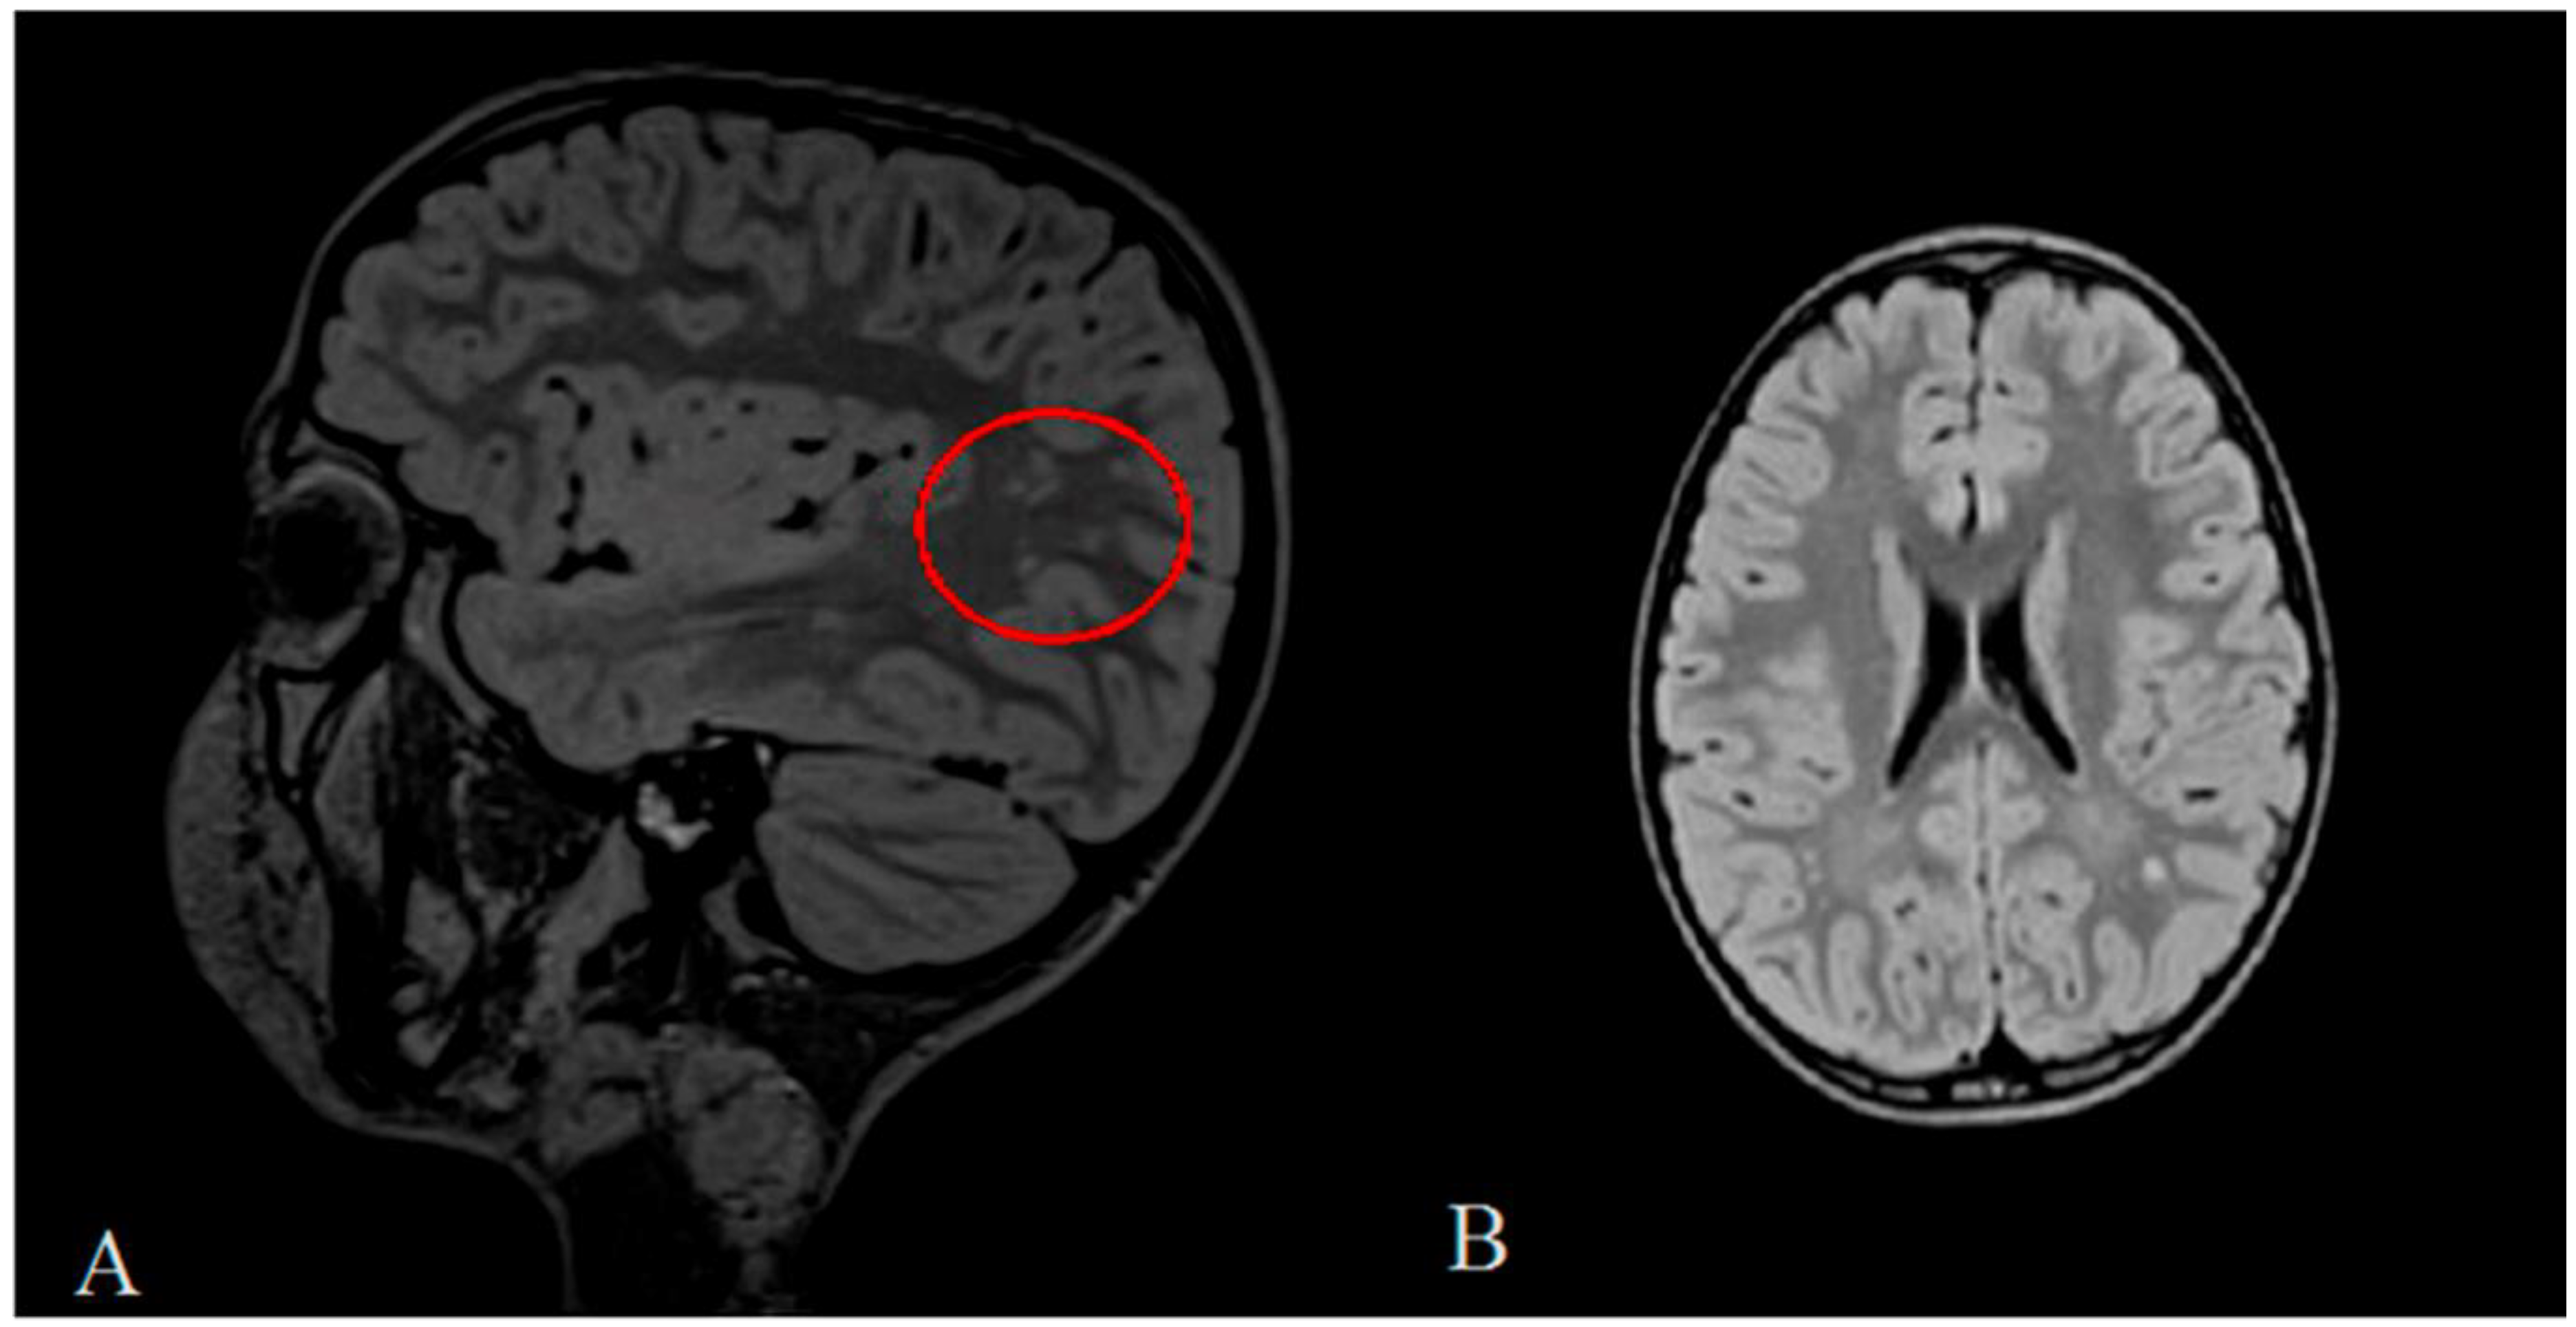

2. Clinical Report